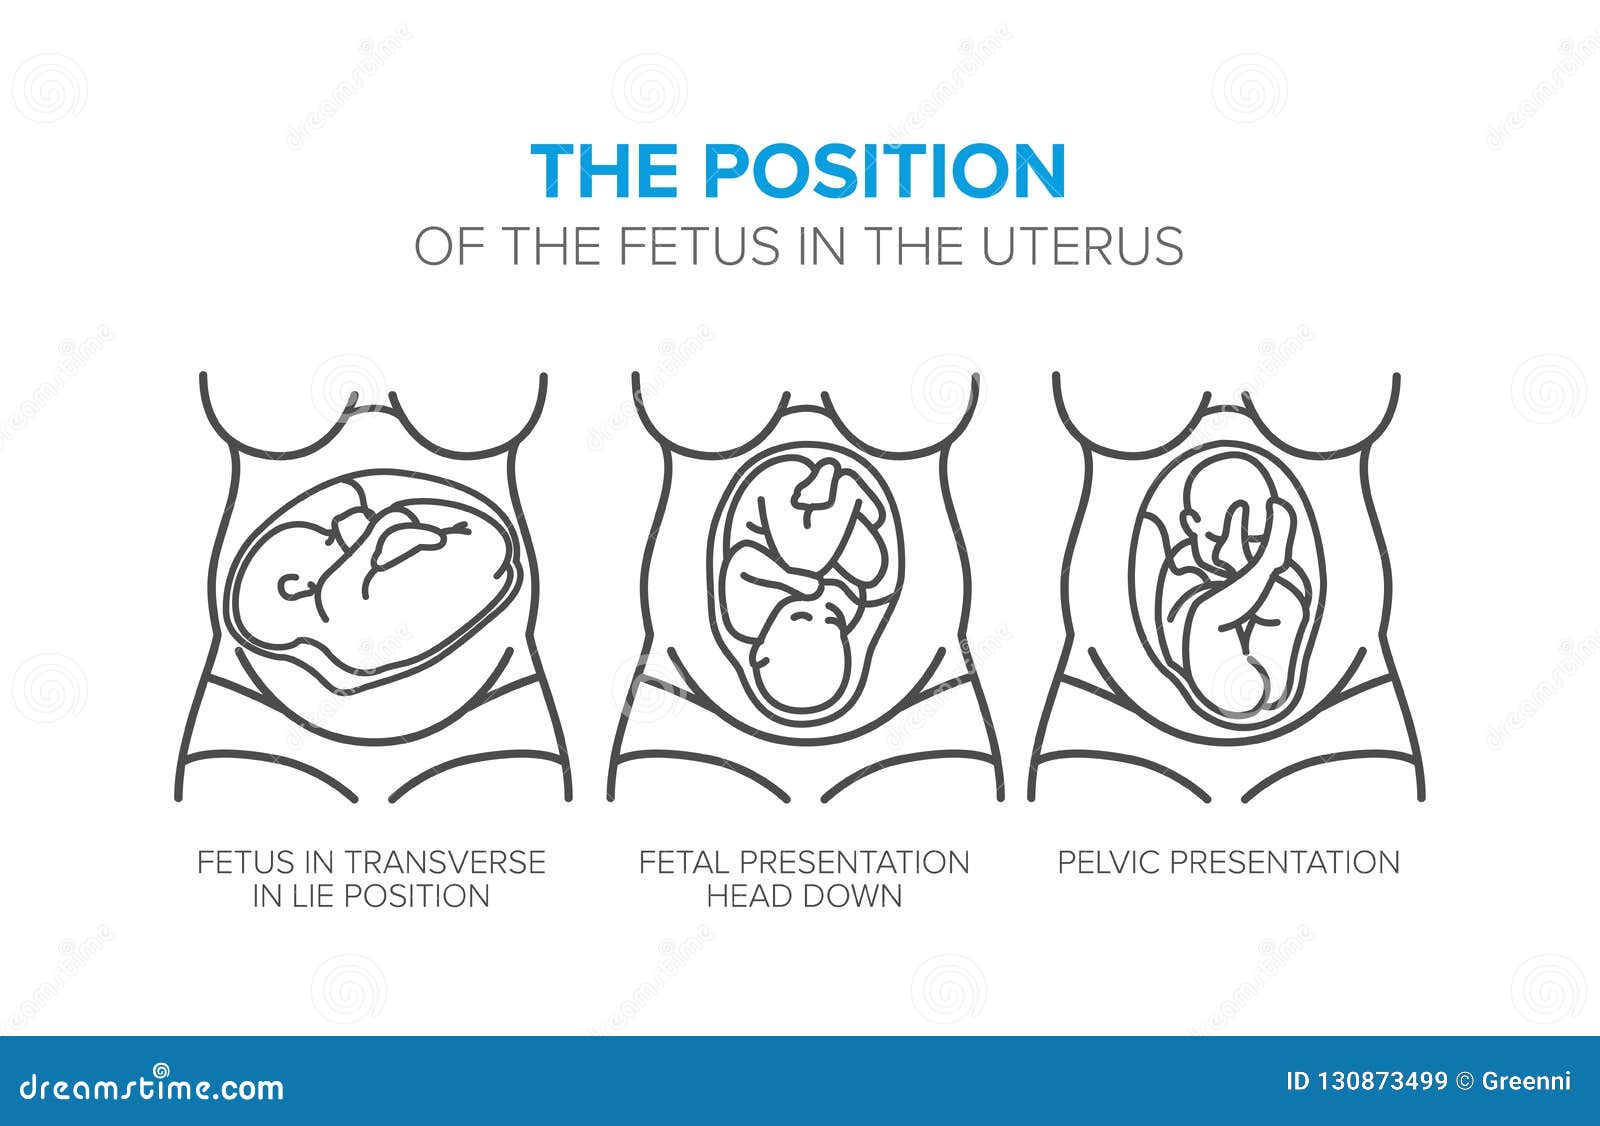

Во время беременности, положение плода имеет большое значение для мамы и малыша. Одним из типичных положений является продольное предлежание головное. В этом положении голова малыша находится внизу, а ножки - наверху. Это положение достаточно распространено и предпочтительно для естественных родов.

Longitudinal Lie and Cephalic position of child

Фото положения плода во время беременности

Ниже приведены несколько фотографий, которые помогут вам визуализировать положение плода во время беременности.